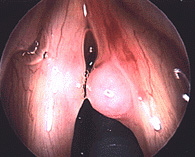

Close up of vocal fold nodule

The picture to the left shows typical vocal fold nodules. (Anterior is to the top, and posterior is the back. Note that they are present on both vocal folds and in this case are actually quite symmetric. The are located about one-third of the way back on the vocal folds.